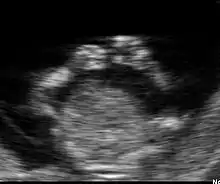

Fœtus à 12 semaines

Dans la plupart des cas, une échographie pratiquée à 12 semaines permet de détecter de nombreuses pathologies. Bien entendu, cette détection dépend de nombreux facteurs qui ne sont pas tous du ressort du médecin. Le surpoids et l'obésité sont actuellement les facteurs limitants les plus importants.

Sur la figure 7 on distingue à gauche une zone intra-abdominale blanche correspondant à l'intestin du fœtus. Dans cette zone blanche, une petite tache noire qui est la vessie. Enfin, à droite des intestins, on peut distinguer le foie et les poumons.

La face est explorable. Les deux orbites sont distinguables ainsi que les deux cristallins. Les membres se distinguent nettement. Le diagnostic d'anomalie des membres est possible à ce stade.

Les malformations graves du cerveau sont détectables comme l'anencéphalie ou l'holoprosencéphalie. Les malformations cardiaques ne sont pas détectables en routine à ce terme.